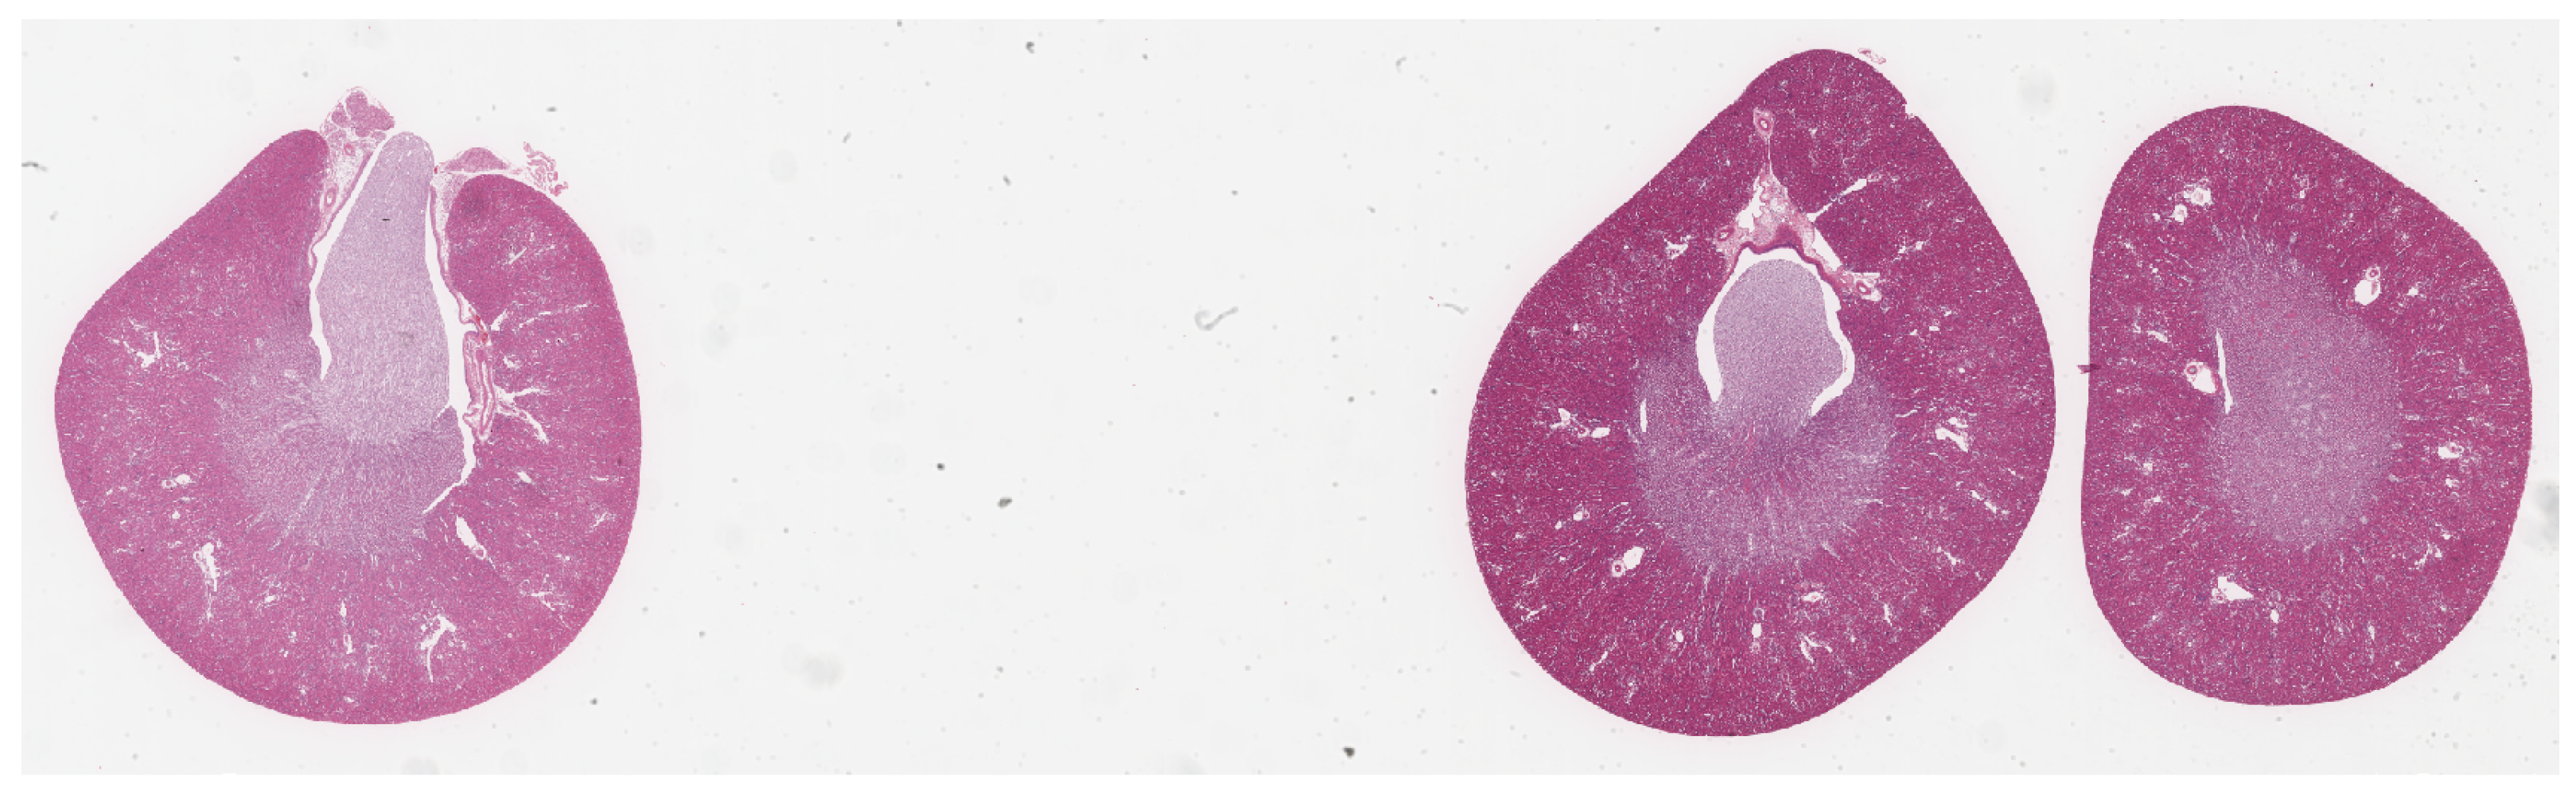

2.1.2. IgA Glomerulus Images for Contrastive Pretraining and Transfer Learning

The IgA glomerulus image dataset comprised periodic-acid-Schiff–stained human pathological images from 313 chronic kidney disease cases treated at Fukushima Medical University Hospital between 2002 and 2018. The digitization of these images was performed with the virtual sliding Leica Aperio Scan Scope, ID number SS7572, Leica Corp., Wetzlar, Germany. The images were digitized at a maximum magnification of 40× and a spatial resolution of 0.25 mmp. The original pathological images were subsequently cropped into patches of 256 × 256 pixels at a magnification of 8×, which corresponds to a spatial resolution of 1.25 mpp. This process resulted in a dataset comprising image patches, inclusive of 7000 glomerulus-containing and 7000 non-glomerulus-containing images. The dataset was then partitioned into training, validation, and test sets in a 7:1:2 ratio. Each set contained images from distinct cases. Figure 2 shows the original WSI from a patient with IgA nephritis.

Figure 2. An original WSI of a patient with IgA nephritis with an actual size of 35,856 × 23,388.